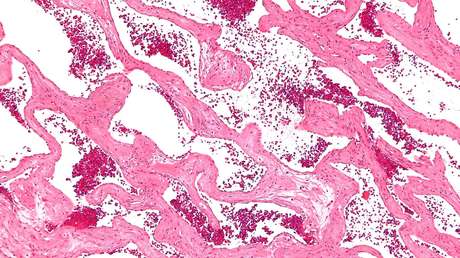

El angioma cavernoso es una enfermedad que ocurre en aproximadamente el 0,5 % o 1 % de la población y presenta anomalías en los vasos sanguíneos del cerebro. Estos pueden causar hemorragias, ataques convulsivos y problemas neurológicos como debilidad de los brazos o las piernas, problemas de vista o equilibrio, o problemas de memoria y concentración.